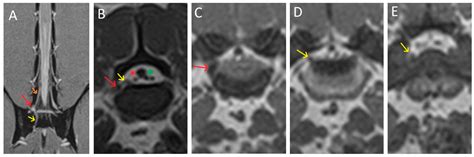

Imaging Studies

Imaging studies, such as X-rays, MRI, and CT scans, can provide detailed images of the spine and surrounding structures. These tests can help identify conditions such as herniated discs, spinal stenosis, and other abnormalities that may be compressing the S1 nerve root.